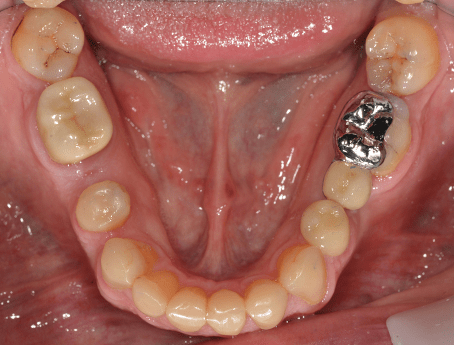

Crowns

Crowns may be used to treat toothwear or broken down teeth. They are often selected where composite has failed, the teeth are too broken down or there is a need to provide a stronger material. This case was managed with surgical crown lengthening and multiple crowns. The lower incisors were treated with composite.